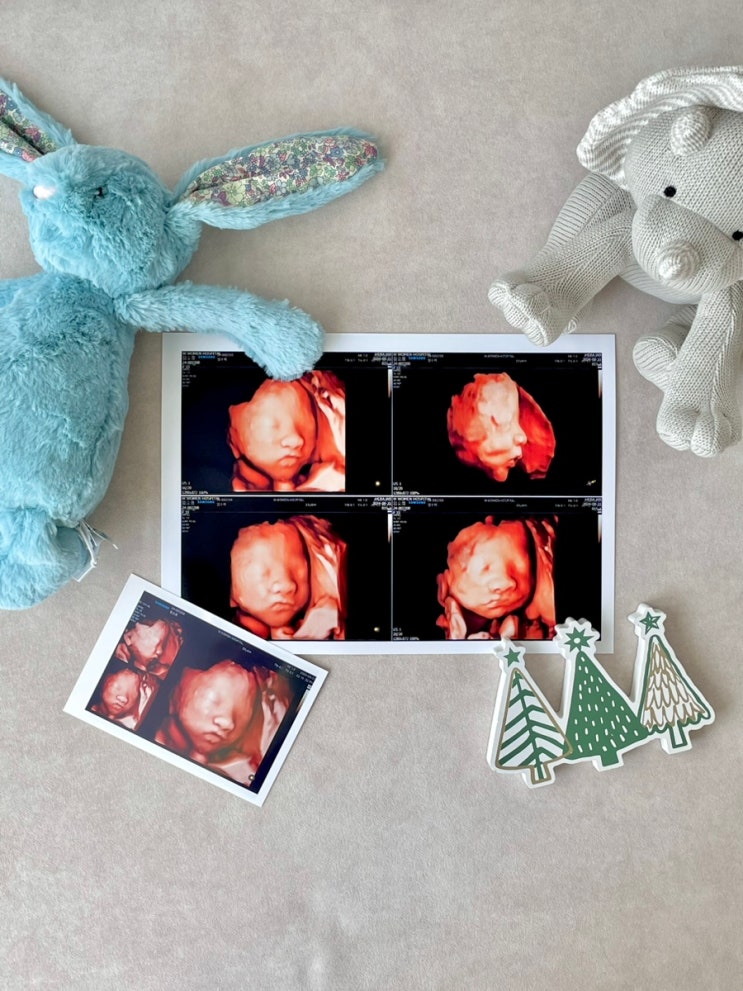

11. 대구 수성구 더블유여성병원(#11. 28주 입체초음파진료 및 카페이용)후기

2024년 8월 31일 토요일 - 오늘 빤짝이 얼굴 보러가는날! 임신하고 성별알기전까진 시간이 정말 안갔는데 ...